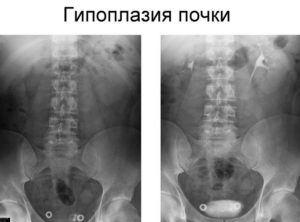

Чтобы назначать лечение при гипоплазии, сначала нужно подтвердить диагноз комплексом диагностических мер. В качестве основного метода в таком случае выступает диагностика ультразвуком. Сканирование помогает определить уменьшение толщины и сокращение почечного объема.

Чтобы выявить аномалии мочевыводящих путей в плане строения, рекомендуется попробовать урографию экскреторного типа. Речь идет о рентгеновском способе диагностики, в рамках которого предполагается введение контрастного вещества в кровь пациента.

В некоторых случаях рекомендуется обратить внимание на томографию магнитно-резонансного типа. Этот вариант диагностики быстрый. Кроме этого, исследование поможет дать оценку не только размерам органов, но получить их трехмерное изображение. Однако такой способ исследования является дорогостоящим, поэтому доступен далеко не всегда.

При отсутствии симптомов гипоплазии почек у взрослых и детей выявить аномалию органа можно случайно при профилактическом обследовании с использованием УЗИ. Если обнаружены признаки патологии, кроме этого метода для выявления степени поражения органа назначают:

- допплерографию;

- рентгенографию с применением контрастного вещества;

- динамическую сцинтиграфию;

- МРТ почек;

- компьютерную томографию.

При ультразвуковом исследовании определяют размеры органа, почечной лоханки, количество и размеры чашечек. УЗИ позволяет выявить пиелонефрит, мочекаменную болезнь. Ребенку даже при отсутствии симптомов обязательно проводят УЗИ, если аномалия есть у его матери.

Состояние кровоснабжения органа, почечных сосудов определяют методом допплерографии – цветового УЗИ.

Аналогичным образом с помощью сцинтиграфии изучают образование и выделение мочи, вводя в кровь безопасное для человека радиоактивное вещество. Специальный прибор периодически фиксирует весь процесс, позволяя выявить степень недоразвития почки.

При МРТ и КТ выявляют патологию, послойно сканируя аномальный орган. МРТ считают более безопасным, так как используется магнитное поле, а при КТ работает рентгеновское излучение и в вену вводят контрастное вещество.